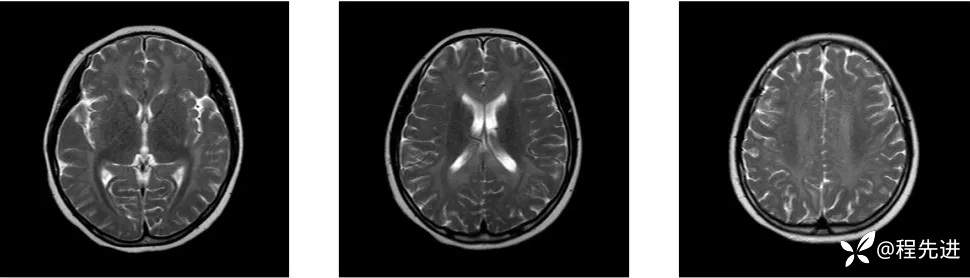

MRI: